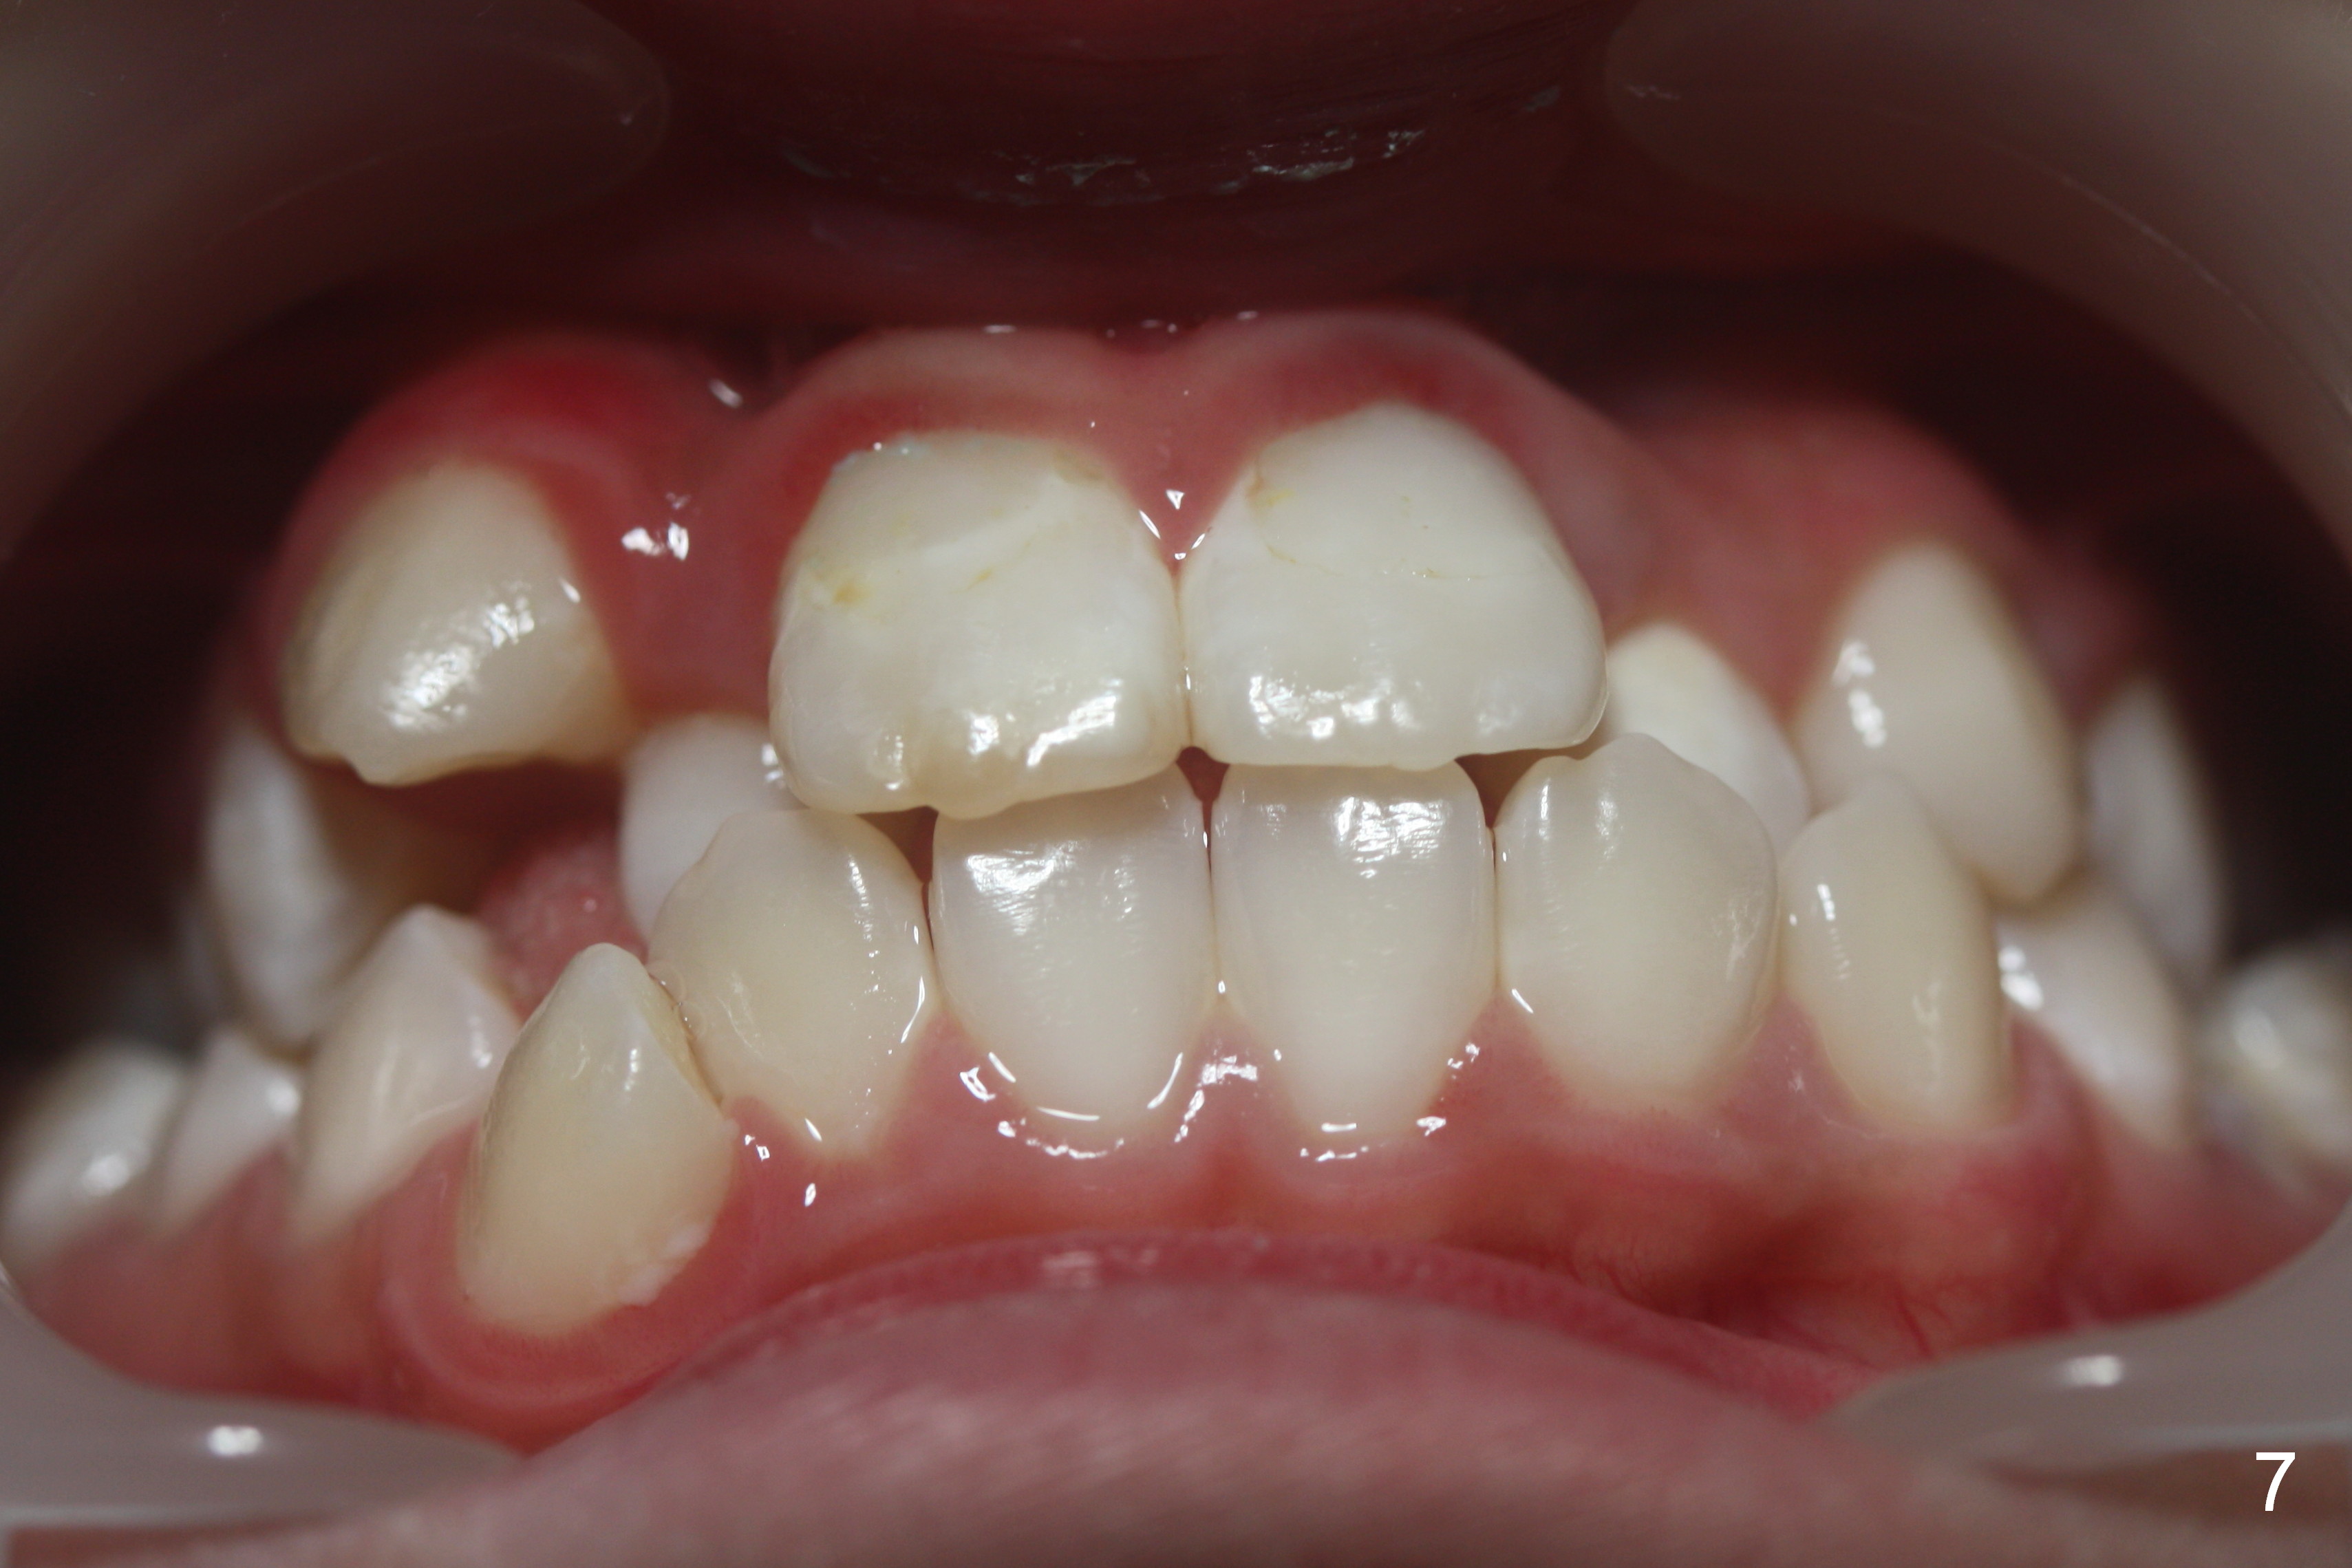

A 10-year-old girl with history of hyper-thyroidism has severe Class I malocclusion. She is ready for treatment. There is mild lip strain (suggesting anterior tooth protrusion, Fig.1,3). The facial and dental midlines coincide (Fig.2). Severe crowding is evident. Extraction orthodontics is indicated, either next to the most crowded areas (UR, LR4, Fig.6) or impacted ones (UL, LL5, Fig.10,11 (mirror view)).